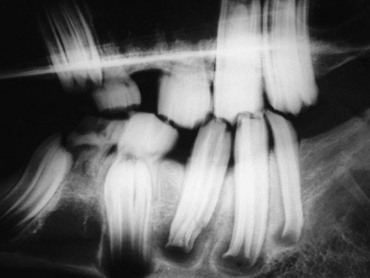

Retention of cheek teeth

Abnormal retention of the remnants of the deciduous CT (termed ‘caps’) can occur in horses between 2 and 4.5 years of age. These deciduous teeth are normally shed at 2.5, 3 and 4 years of age respectively, for the 06s, 07s, and 08s, but there can be much individual variation in the timing of deciduous cheek tooth shedding.33,34 If the deciduous teeth are loose, they may abnormally stretch or tear periodontal ligaments or gingival attachments during mastication, causing short-term oral discomfort. Affected horses may display headshaking, quidding, resistance to the bit, and occasionally loss of appetite for a couple of days, until the loose teeth are shed. Such clinical signs of oral discomfort in 2–4-year-old horses warrant careful oral examination for evidence of deciduous teeth that are loose or have a distinct space between deciduous and permanent teeth (Fig. 8.26). If loose deciduous CT are found, they can be removed using specialized ‘cap’ extractors or small CT forceps (Fig. 8.27). Even if not loose, some clinicians advise that temporary CT should be extracted, if the corresponding contralateral ‘cap’ has already been shed.

image

Fig. 8.26 A distinct margin is apparent between the deciduous and permanent mandibular CT in this skull, indicating the former is ready to be shed, and is retained by periodontal attachments on one side only (arrow).